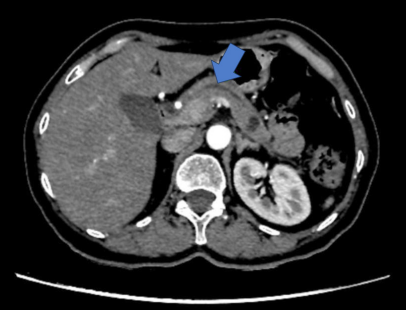

La ecografía abdominal inicial mostró una vesícula sin litiasis en su interior, sin dilatación de la vía biliar intra y extrahepática, y un páncreas de forma y tamaño conservado. Ante la persistencia de la sintomatología se indicó una TC de abdomen y pelvis, con hallazgos de páncreas de tamaño, contornos y densidad normal, pero en el cuerpo se identificaba una imagen hipodensa redondeada, de 12,8 mm de diámetro, de contornos levemente lobulados, aspecto quístico y, al parecer, en comunicación con el conducto pancreático principal (Figura 1), el cual se encontraba discretamente dilatado en toda su extensión, con un diámetro de 3 mm, y emergía directamente a la segunda porción del duodeno, configurando páncreas divisum como variante anatómica (Figura 2).